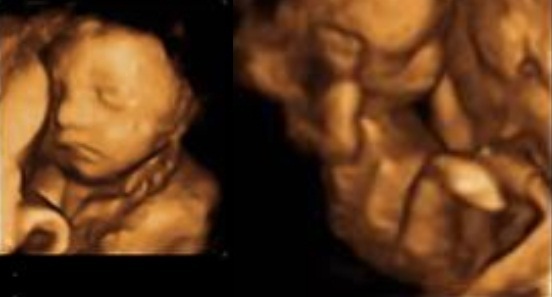

Here we go :) Left one is 28 weeks, right pics 16 weeks pic :P (Really hoping I'm not outing myself badly here!!)

Great photos's plinky I think beanie is looking much more baby than alien :)

Aww plinky how beautiful! I'm having a 3d/4d scan at 28 weeks I can't wait to see her little squidgy face!!!

Ahhh plinky they are beautiful....

Aww plinky what a cute little face

Thank you :) I know it sounds daft but it's astonishing how much she's grown already - can't believe I still hav 12-14 weeks before I can meet her! I want to give her cuddles now :D